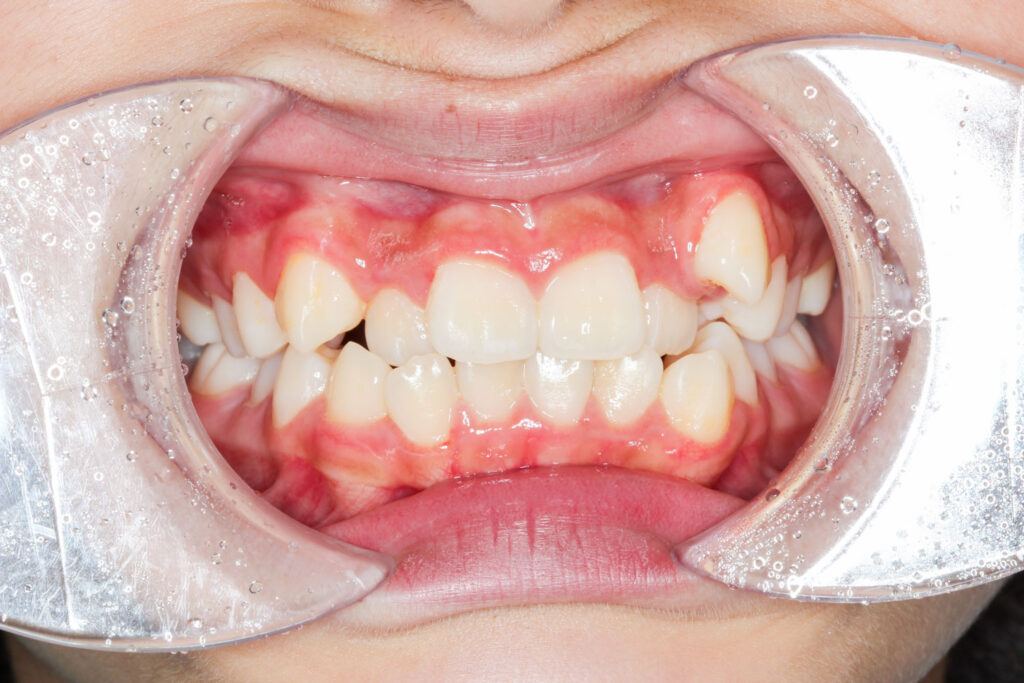

Before

年齢 10代

治療装置 上下とも裏側の矯正装置(フルリンガル)

治療内容 非抜歯

治療期間 2年8か月

リスク 歯の移動に伴う痛み、歯肉退縮、歯根吸収、歯肉炎、虫歯

主訴 八重歯が気になる

症状 叢生(ガタガタ)

治療回数 35回程度

総額費用 140万円程度